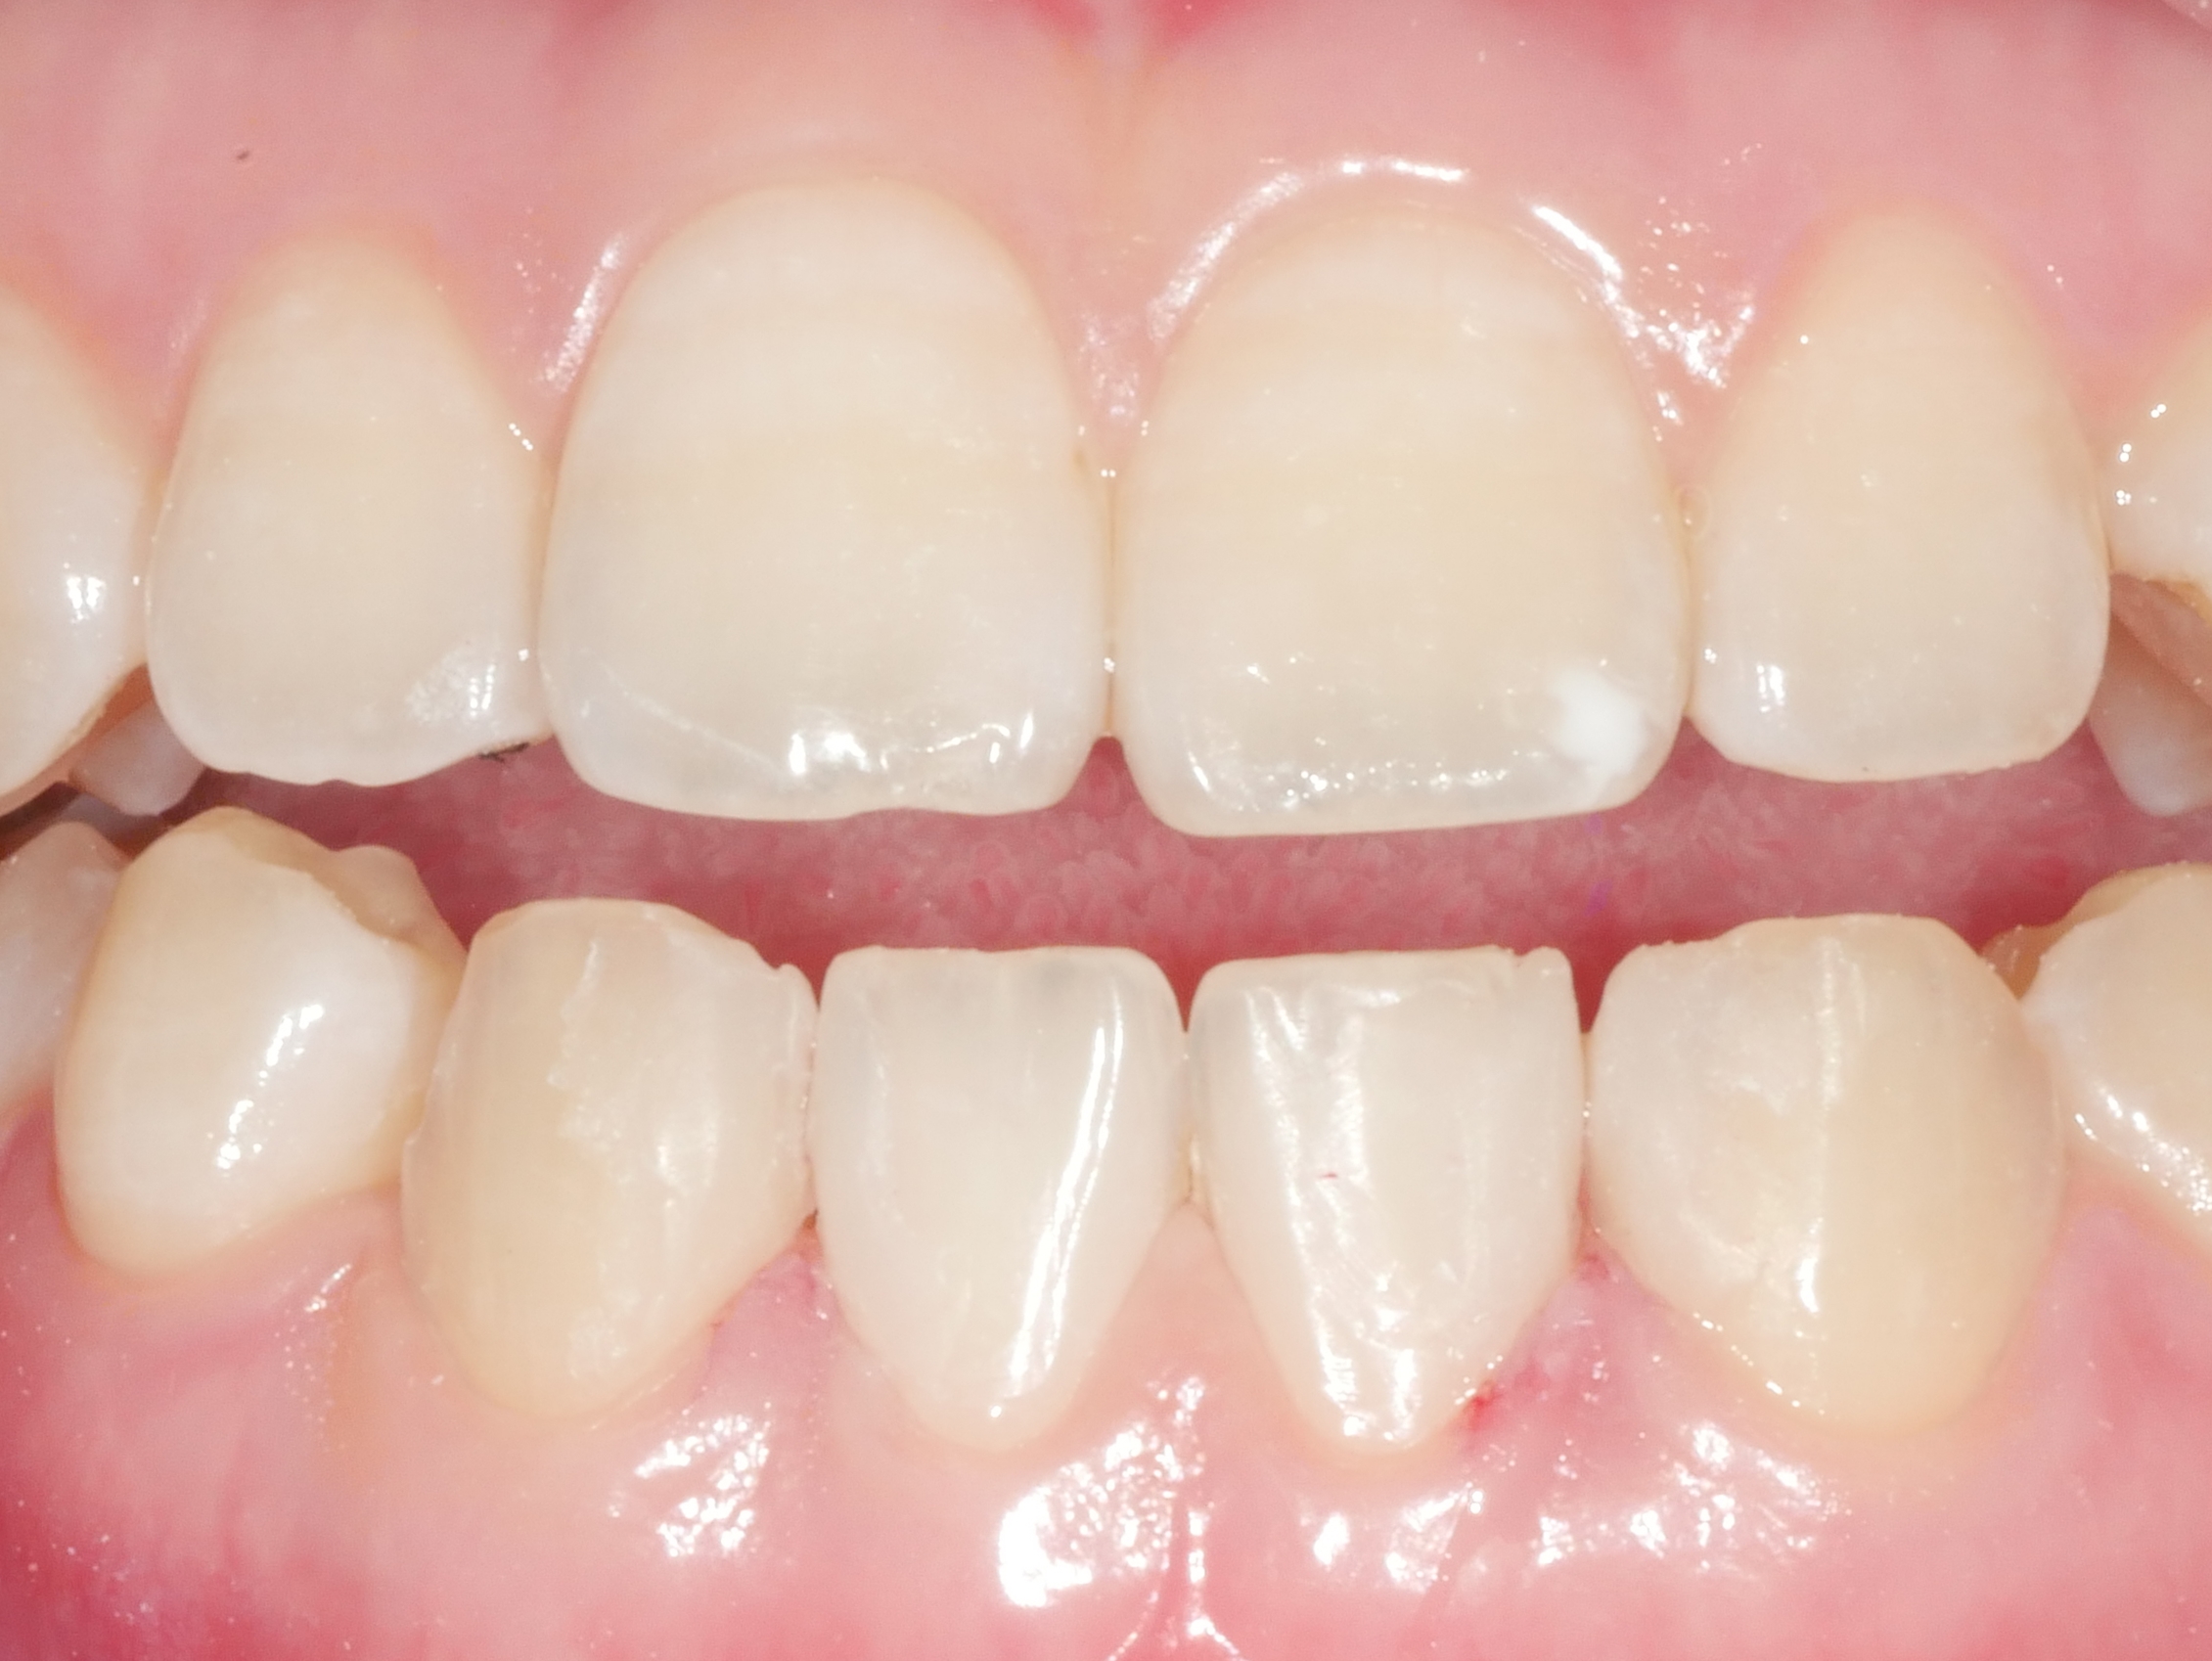

CASE.6 치아미백

치료전 2022.06.29 / 치료후 2022.07.06